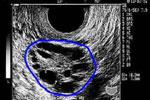

Τη λήψη λεπτομερούς ιατρικού και οικογενειακού ιστορικού, τη φυσική εξέταση από τον ιατρό, την εξέταση ούρων για τον αποκλεισμό της πιθανότητας εγκυμοσύνης ως αίτιο της αμηνόρροιας και τις εξετάσεις αίματος. Με τις τελευταίες ελέγχονται τα επίπεδα των λιπιδίων, του σακχάρου και των ορμονών. Οι εξετάσεις ολοκληρώνονται με την εξέταση της λειτουργίας του θυροειδή και με το κολπικό υπερηχογράφημα.

Σε αυτό οι ωοθήκες φαίνονται μεγαλύτερες σε μέγεθος με πολυάριθμες κύστεις σε ποσοστό μεγαλύτερο από 90% των γυναικών με PCOS.Η εξέταση όμως είναι μόνο για την επιβεβαίωση του συνδρόμου καθώς υπάρχει ένα ποσοστό 8-25% γυναικών χωρίς το PCOS αλλά με παρουσία τέτοιων ευρημάτων στο υπερηχογράφημα.